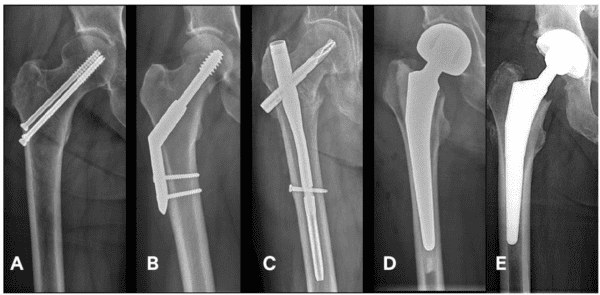

Welke operatie krijgt u?

Het type breuk, uw leeftijd, hoe goed u kunt bewegen en uw algemene conditie: samen bepalen ze welke operatie u kunt krijgen.

De operaties die het meest voorkomen bij een gebroken heup staan hieronder:

| A | Drie holle schroeven in de kop (CHS). |

| B | Een plaat tegen het bot met een grote schroef in de kop (DHS). |

| C | Een pen in de mergholte met een spiraal in de kop (PFNA). |

| D | Een vervanging van de kop van het bovenbeen (KHP). |

| E | Een vervanging van de kop van het bovenbeen en de kom van het bekken (THP). |

De operatie die waarschijnlijk bij u gaat plaatsvinden, is (omcirkelen door de arts):

| A | B | C | D | E |

Het kan zijn dat de arts tijdens het opereren toch kiest voor een andere soort operatie. Na de operatie zullen we u dan uitleggen waarom we dit hebben gedaan.